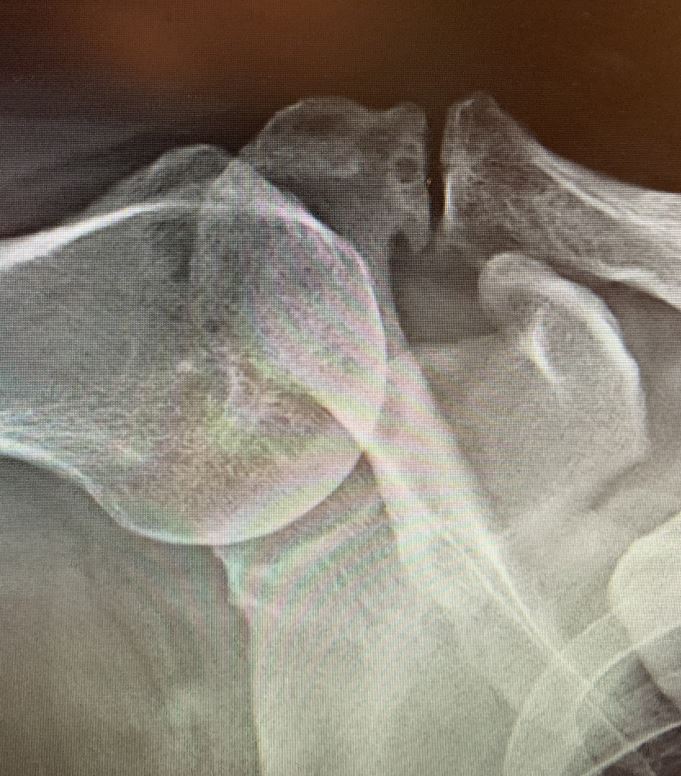

Das Schultergelenk verweigert den Dienst

Röntgenaufnahme Schultergelenk/© A. Schuh, Die Leitlinien für Ärztinnen und Ärzte, Facharzttraining Allgemeinmedizin, Eine Hand die schreibt mit Computer daneben/© Chainarong Prasertthai / Getty Images / iStock (Symbolbild mit Fotomodell), Ältere Frau mit schmerzender Hand/© Evrymmnt / stock.adobe.com (Symbolbild mit Fotomodell), Mädchen bekommt eine Spritze in den Oberarm/© Photographee.eu / stock.adobe.com (Symbolbild mit Fotomodell), Ältere Frau mit Hanteln/© Satjawat / Stock.adobe.com (Symbolbild mit Fotomodell), EKG befunden mit System - EKG Essential/© Springer Medizin Verlag GmbH